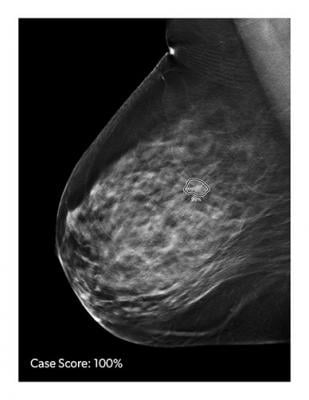

3d Mammography Significantly Reduces Breast Biopsy Rates

3d Mammography Catches Breast Cancer Sooner Reduces False Results